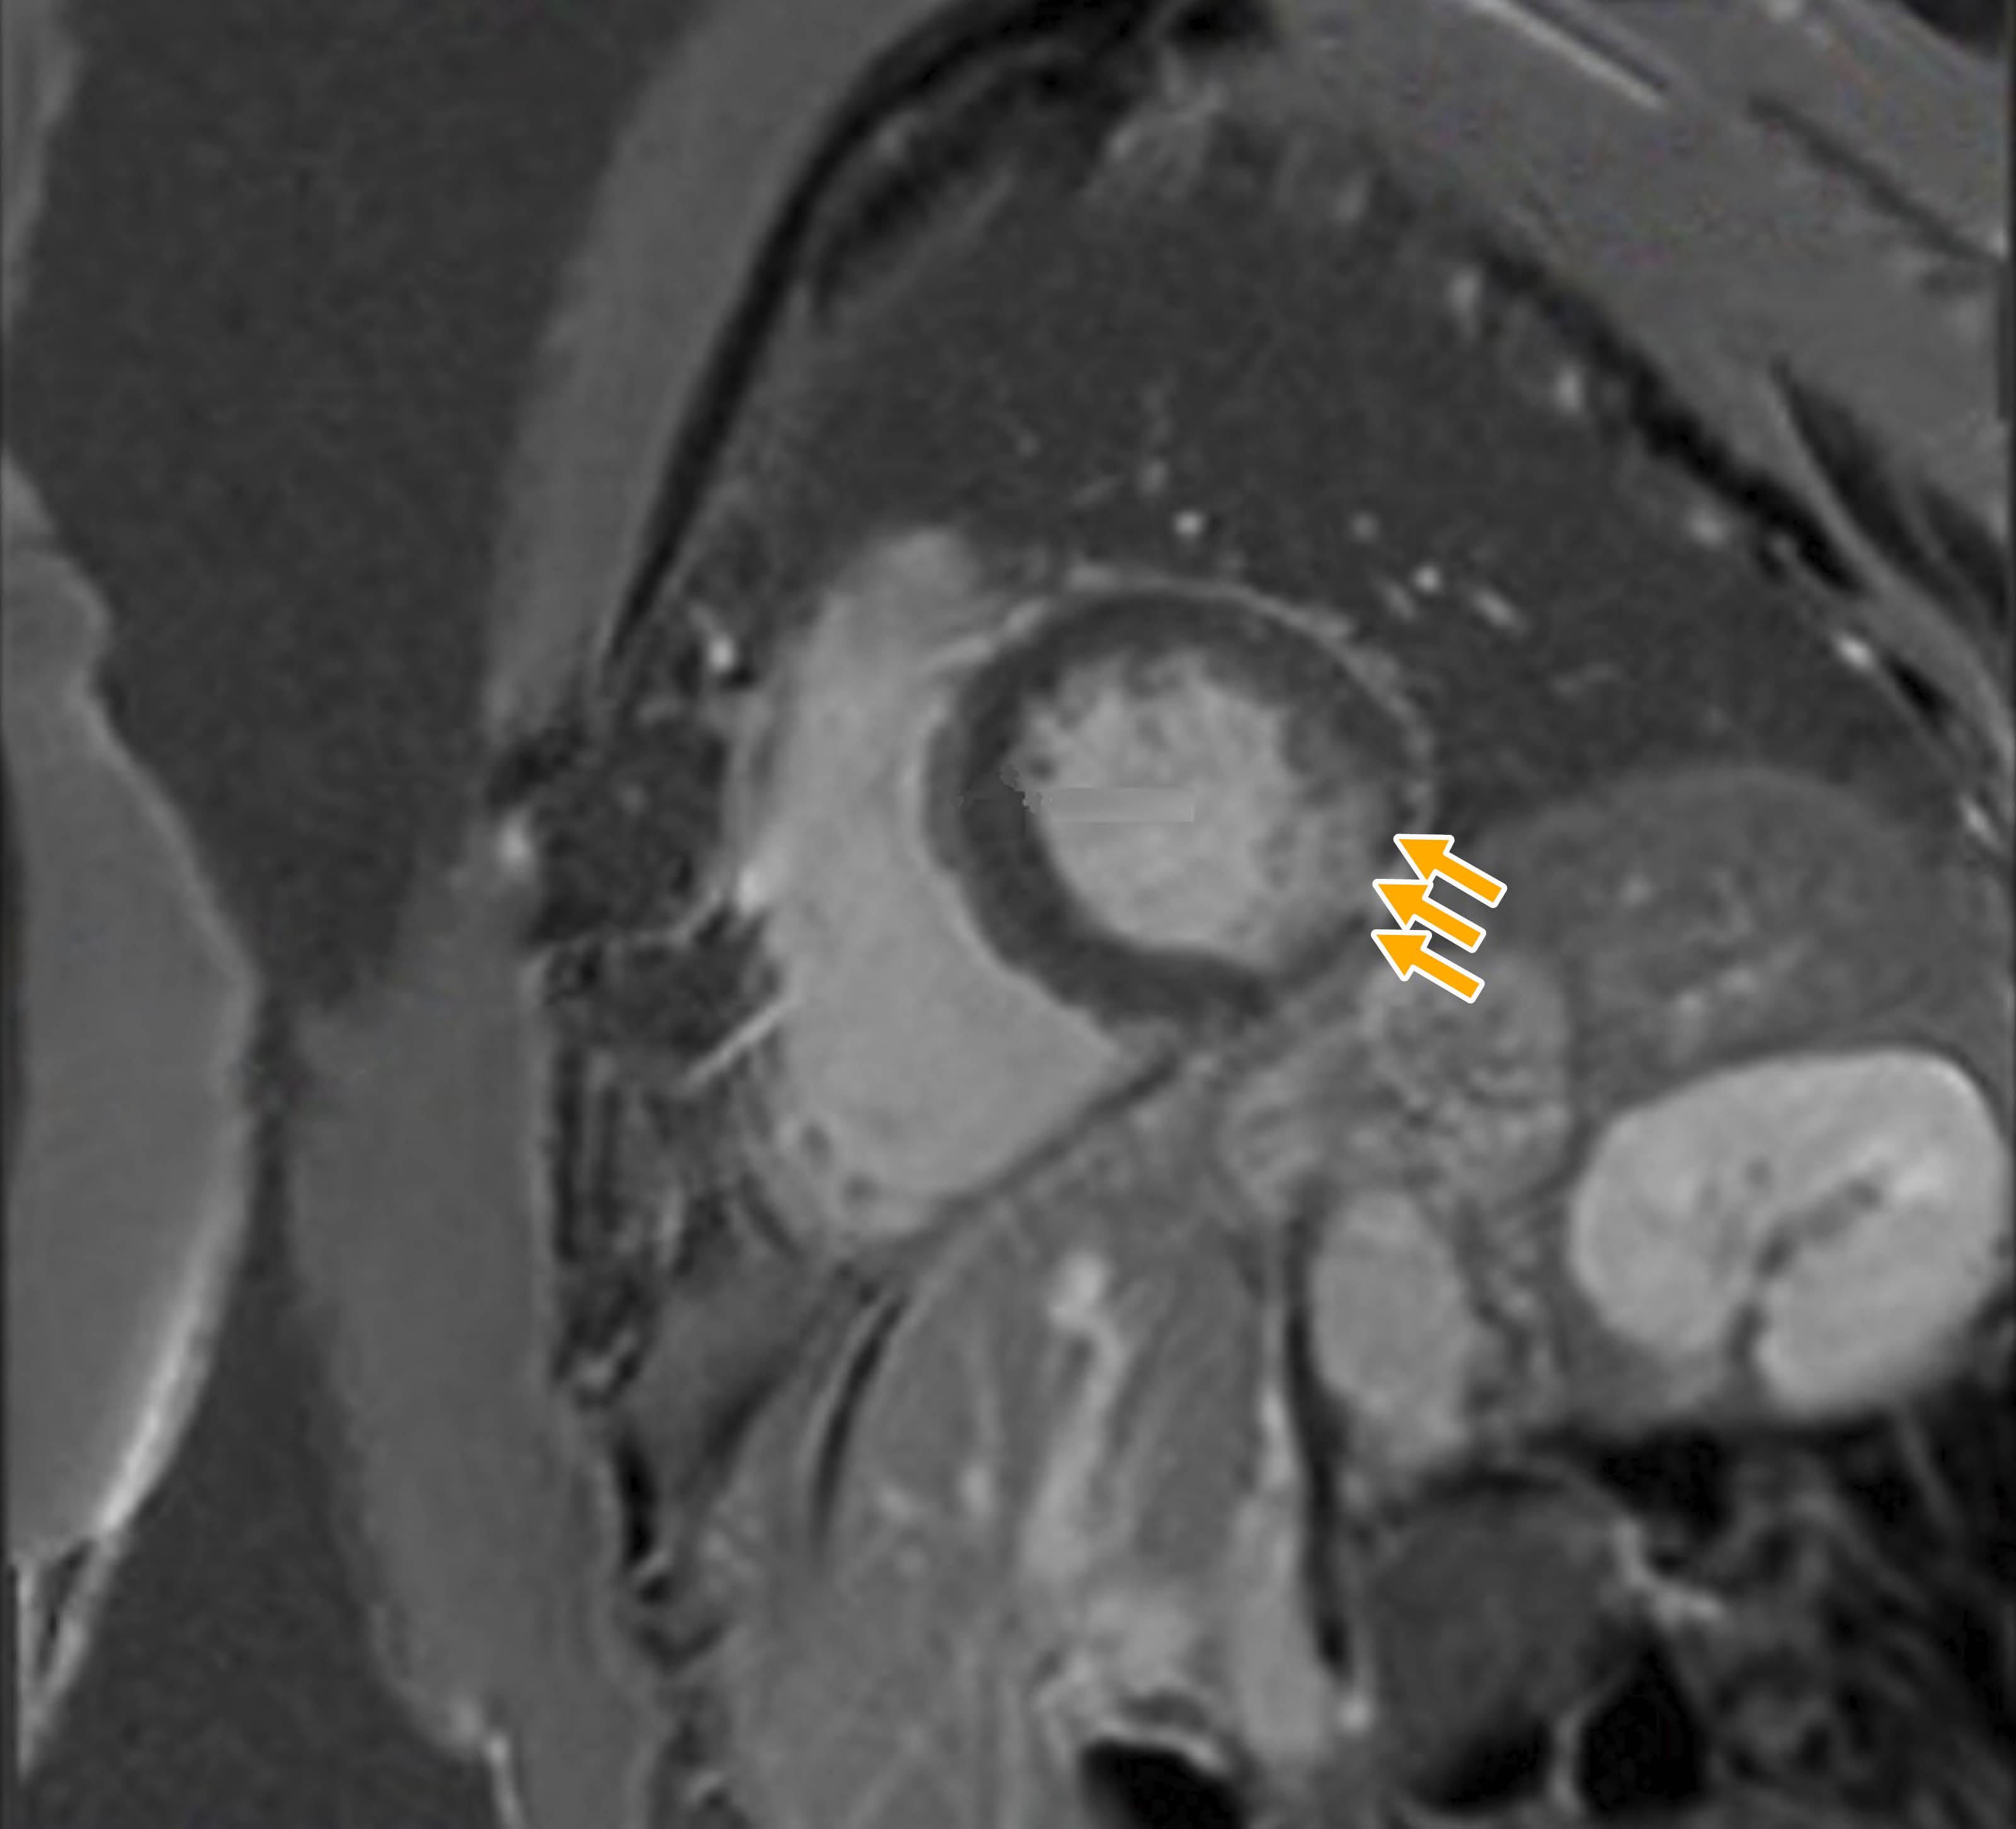

Introducción: las complicaciones agudas son frecuentes tras una sustitución o anuloplastia de la Válvula Mitral (VM). La isquemia inducida por la estenosis de la Arteria Circunfleja (ACx) causada por las suturas de la anuloplastia de la VM es la complicación aguda más frecuente. Presentación del caso: una mujer de 69 años con anuloplastia de la VM realizada con éxito cinco años previos se presentó con una historia de cuatro meses de dolor precordial opresivo al esfuerzo. Un ecocardiograma de esfuerzo mostró isquemia e hipocinesia de la pared inferolateral. La angiografía coronaria por tomografía computarizada reveló estenosis extrínseca en el tercio medio de la ACx, cerca del anillo de anuloplastia, en consonancia con los hallazgos de la angiografía coronaria. La resonancia magnética cardiaca demostró hipocinesia de la pared inferolateral y necrosis transmural de la pared inferolateral basal. Se realizó intervención coronaria percutánea con Ultrasonido Intravascular (IVUS) que mostró la estenosis. Realizamos angioplastia y colocación de stent con IVUS post-stent que mostró una adecuada aposición. El paciente fue dado de alta dos días después con tratamiento médico óptimo. La estenosis crónica de la ACx tras anuloplastia de la VM es extremadamente rara, con sólo cuatro casos descritos en la literatura. Conclusión: un enfoque multimodal, que incluye el uso de IVUS, puede ayudar a identificar el mecanismo de isquemia de una oclusión crónica de la ACx y en la toma de decisiones clínicas para un abordaje apropiado.

Figura 2